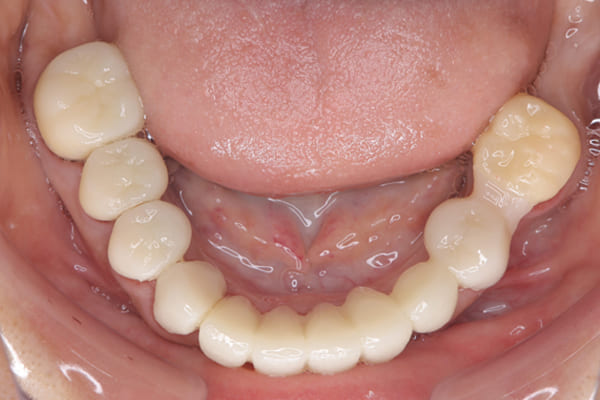

下顎治療前

下顎治療後

治療前の入れ歯の奥歯は、治療後の義歯と比較しても分かるように、歯が削れ平らになった状態です。

これにより奥歯のかみ合わせは低くなり、前歯のみが強くあたり、かみ合わせにより上の前歯大きな負担がかかっていたことにより、上の前歯が折れたことが考えられます。